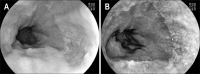

Methods: Endoscopic images of 51 patients with gastroesophageal reflux disease (GERD) symptoms were obtained with conventional endoscopy and optimal band imaging (OBI). Endoscopists were divided into an expert group (16 gastroenterologic endoscopic specialists guaranteed by the Korean Society of Gastrointestinal Endoscopy) and a trainee group (individuals with fellowships, first year of specialty training in gastroenterology). All endoscopists had no or minimal experience with OBI. GERD was diagnosed using the Los Angeles classification with or without OBI.

Figures